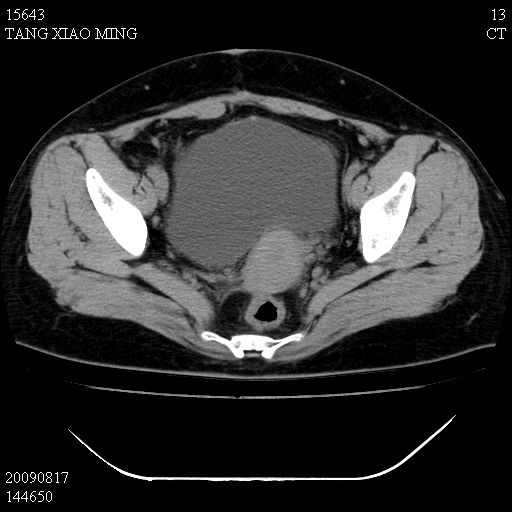

标题: CT21692:盆腔病变

女,33岁,右下腹痛2年余,既往宫外孕病史,如在我院手术,结果下周公布,

可能的诊断。1子宫内膜异位【子宫腺肌症并右卵巢巧克力囊肿】;2 右卵巢囊腺瘤。子宫肌瘤

1)考虑卵巢巧克力囊肿,不排除卵巢囊腺瘤。2)子宫肌瘤可能。

卵巢囊腺瘤,子宫肌瘤,直肠壁厚,不除外占位.